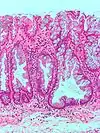

| Hyperplasique | Cryptes dentées non-ramifiées | Non | ![]() |

Hyperplasique polypose syndrome | |

| Adénome dentelé sessile | Semblable à hyperplasique avec hyperserration, bases des cryptes dilatées/ramifiées, des cellules de mucine apparents à la base des cryptes | Oui | ![]() |

||